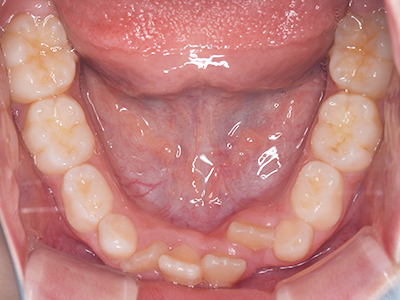

歯並びの相談に来られるお子様は、口呼吸をしているケースが多く、これが歯並びに大きな影響を与えています。

↓ - 下あごが狭くなる・下あごの位置が悪くなる

ないき歯科クリニックでは、上あごの成長不足を補い、鼻呼吸を獲得しつつ歯列を整え、将来のお口をより健康な状態にすることをゴールに定める矯正治療をおこなっています。